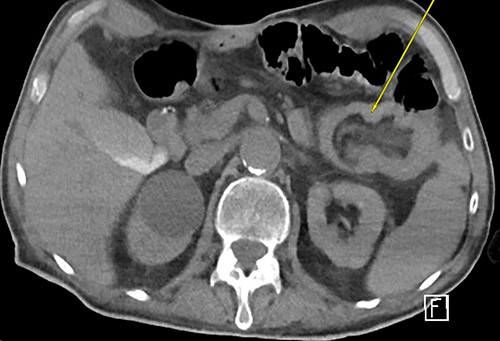

Three weeks later, he presented with a JT obstruction. Multiple attempts using carbonated fluids, enzymes and mechanical brushing failed to clear the obstruction. A computerized tomography of the abdomen and pelvis (CTAP) confirmed the position of the JT and demonstrated telescoping of a long 17 cm segment of jejunum starting from the tip of the JT as lead point (Fig. 1). The JT was removed in hopes of resolution. However, repeat CTAP showed persistent intussusception with mesenteric fat stranding, and possible intestinal ischemia (Fig. 2).

Repeat CTAP s/p JT removal revealed persistent J–J intussusception (yellow arrow).